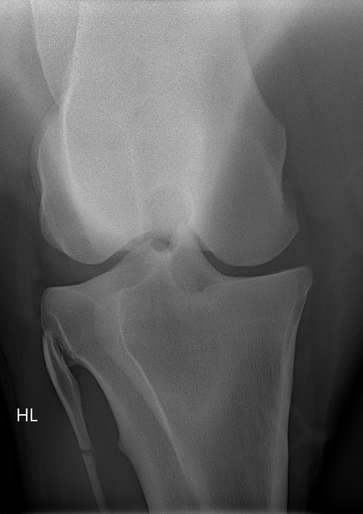

• Röntgen zur Darstellung knöcherner Veränderungen